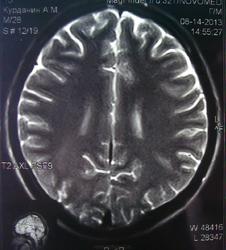

При изучении МРТ снимков головного мозга невролог указала на наличие маленьких очажков на коре головного мозга, порекомендовав обратиться за лечением к нейрохирургам. Голова также продолжает болеть, еще стали кисти рук неметь и прочие симптомы. Можете ли вы указать, имеются ли эти маленькие очажки на коре головного мозга и где именно?

Алексей, очагов достоверно не вижу, а вот на верхнечелюстную пазуху нужно обратить внимание-есть ее воспалительные изменения в виде утолщения слизистой.

а какие либо гематомы видите? просто лечащий врач невролог, указал наличие маленьких очагов воспаления на коре головного мозга!!! Посмотрите пожалуйста повнимательнее снимок 2/6?имеется ли не заращение заднего апофиза тела С5?

а какие либо гематомы видите? просто лечащий врач невролог, указал наличие маленьких очагов воспаления на коре головного мозга!!! Посмотрите пожалуйста повнимательнее снимок 2/6? имеется ли не заращение заднего апофиза тела С5?